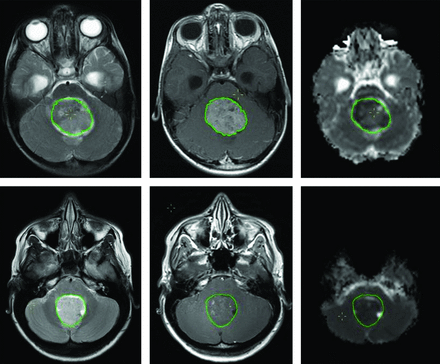

Because we only included preoperative MR imaging, acquisition was undertaken by using standard pediatric neuro-oncologic protocols on several scanner platforms: 1.5T Signa (GE Healthcare, Milwaukee, Wisconsin); and 1.5T Intera or 3T Achieva (Philips Healthcare, Best, the Netherlands). For this analysis, Gd-enhanced spin-echo T1WI (TR = 598–647 ms, TE = 12–14 ms, and 0.4–0.5 × 0.4–0.5 × 4.0–5.0 mm3 voxel size), fast spin-echo T2WI (TR = 3000 ms, TE = 14–85 ms, and 0.4–0.5 × 0.4–0.5 × 4.0–5.0 mm3 voxel size), and diffusion data were used. Diffusion data were obtained with different sequences, ranging from 3-direction diffusion-weighted imaging to 15-direction diffusion tensor imaging, by using B0 = 0 s/mm2 and either bmax = 1000 s/mm2 or bmax = 800 s/mm2, TR = 4883–5800 ms, TE = 59–89 ms, and 1.9–2.0 × 1.9–2.0 × 3.0–4.0 mm3 voxel size. Missing data or exclusion due to motion artifacts reduced the total number of cases per imaging sequence (Table 3). ADC maps were generated by using the FMRIB Software Library toolbox (http://www.fmrib.ox.ac.uk/fsl/). Two sample cases can be seen in Fig 1.

T1WI+Gd (left), T2WI (middle), and ADC map (right) of an anaplastic (top) and classic MB. The overlaid region of interest (inside the green outline) is used to derive shape features and to calculate histogram and texture features for each image sequence.